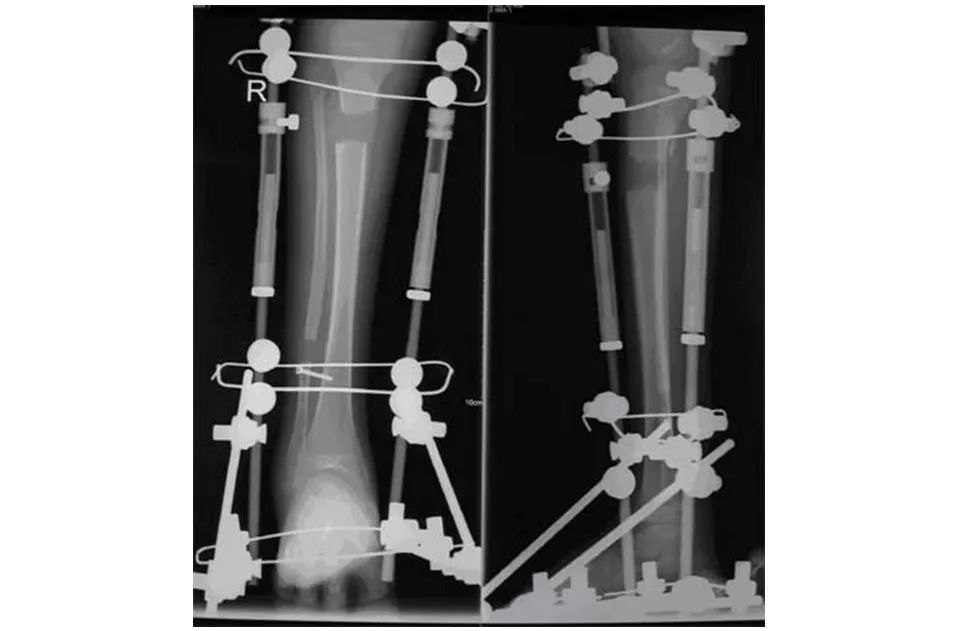

外固定器固定

1.外固定架的优点

(1)术中:操作简便灵活;可操作性极强;适用人群大;适应症广;微创,不剥骨膜;固定较可靠;有内固定无法替代的适用情况。

(2)术后:允许再调整;可改变固定刚度,消除应力遮挡,增加生理刺激;可早期活动;愈合快,并发症少;利于换药、观察。

(3)其他:价格低廉;治疗周期短;去除过程简单。

2.外固定架的缺点

(1)外观差,生活不便

(2)术后管理较繁琐

(3)人类的恐惧感

(4)并发症——钉道渗液、感染;断针;皮肤压迫性坏死与神经、血管损伤;骨折延缓愈合与不愈合。

(5)没有内固定可靠

(6)外固定架治疗长骨骨折存在着固定欠牢固的可能,而固定的稳定性小足可以直接导致骨折延迟愈合和畸形愈合的发生。